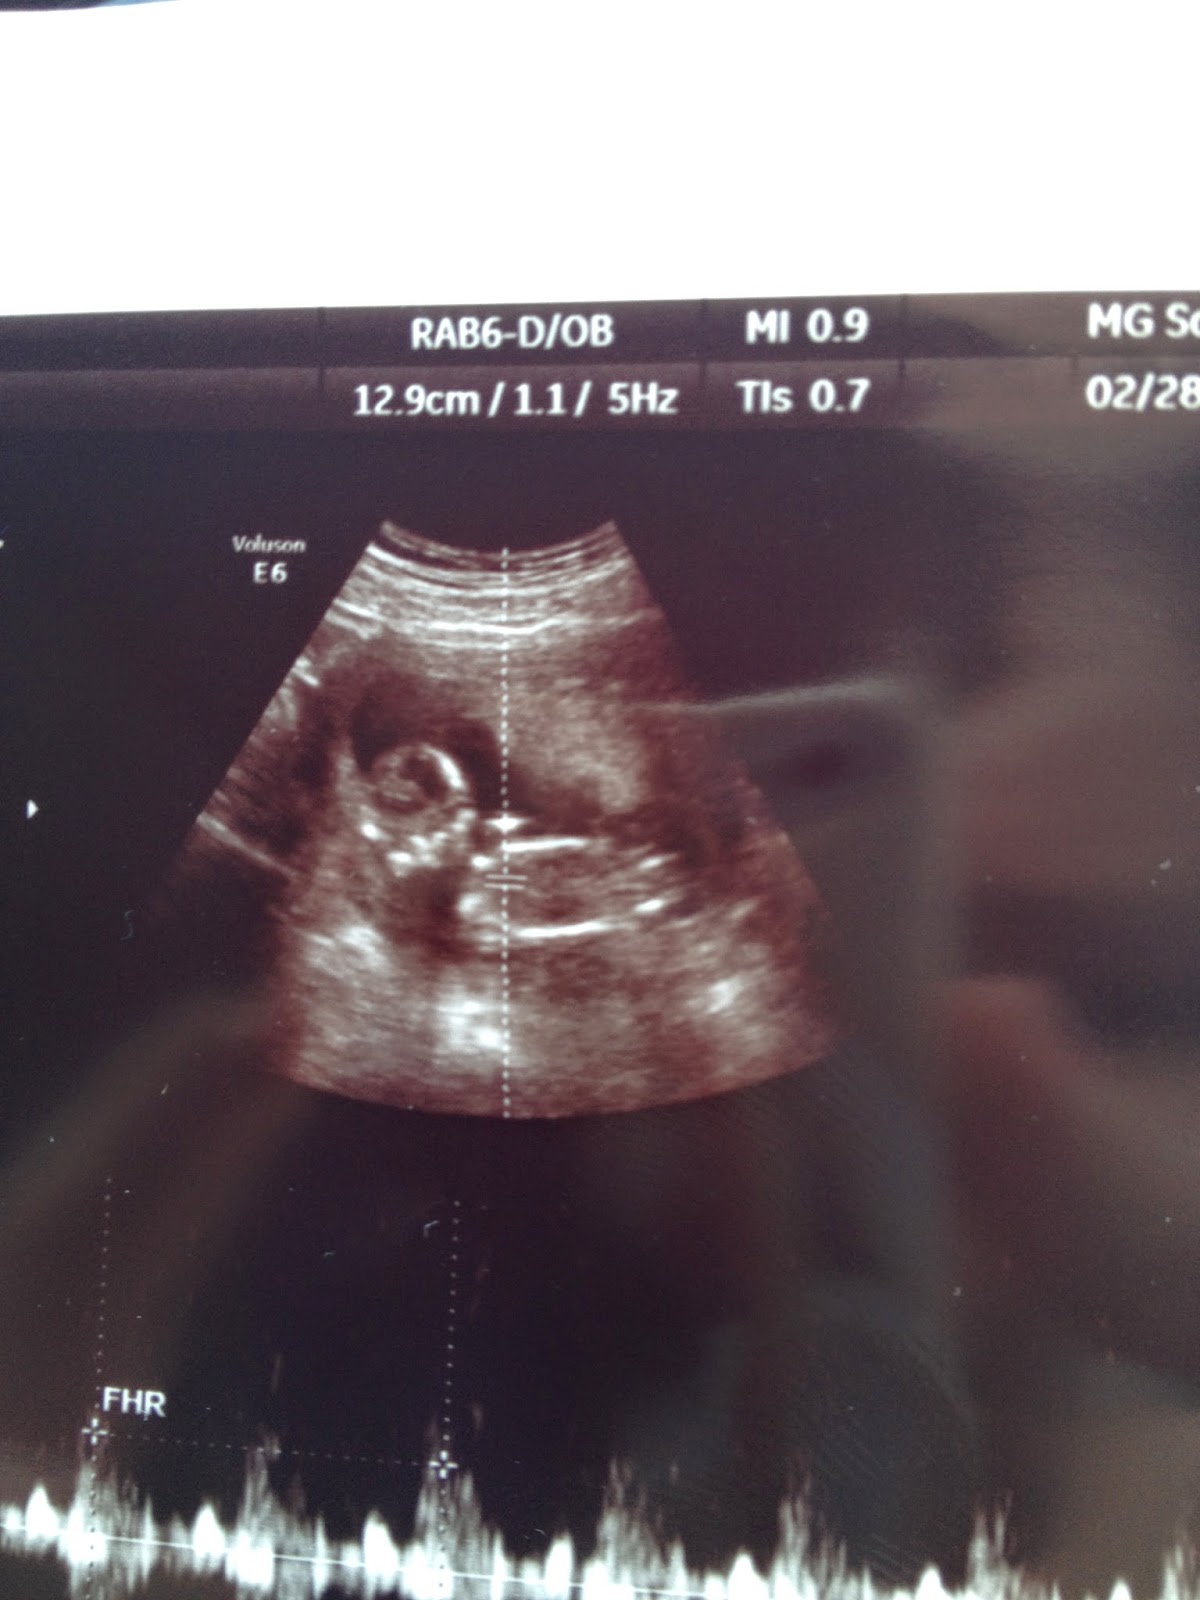

20 week Ultrasounds